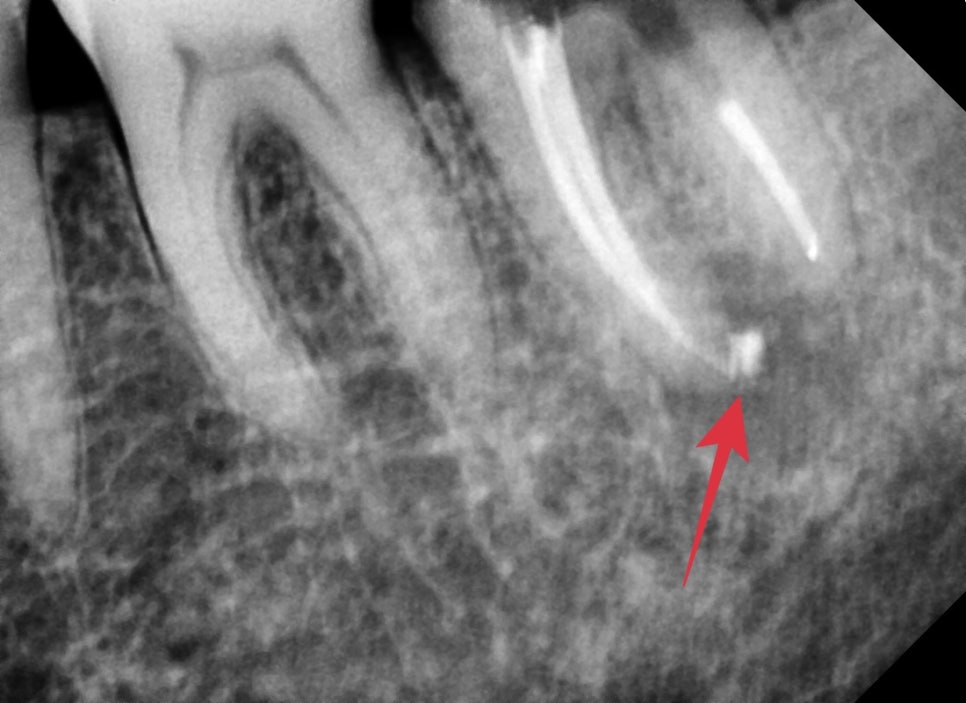

신경치료가 끝난 직후의 엑스레이 사진입니다.

염증이 심했던 치아는 뿌리끝 쪽이 신경관을 밀봉하는 재료가

화살표와 같이 뿌리끝까지 밀려나오며 바깥쪽까지 밀봉해 주는 경우가 있습니다.

물론 해당 재료는 생체친화적이기 때문에 추후 일부는 흡수가 되기도 합니다.

신경치료가 마무리된 후 엑스레이 사진입니다.

첫 번째 케이스와 마찬가지로 의도하지는 않았지만

뿌리 쪽으로 충전재가 뿌리를 감사고 있는 모습을 보이고 있습니다.

염증에 의해 흡수된 치아 주변 뼈는 추후 천천히 차기를 기대해 보겠습니다.